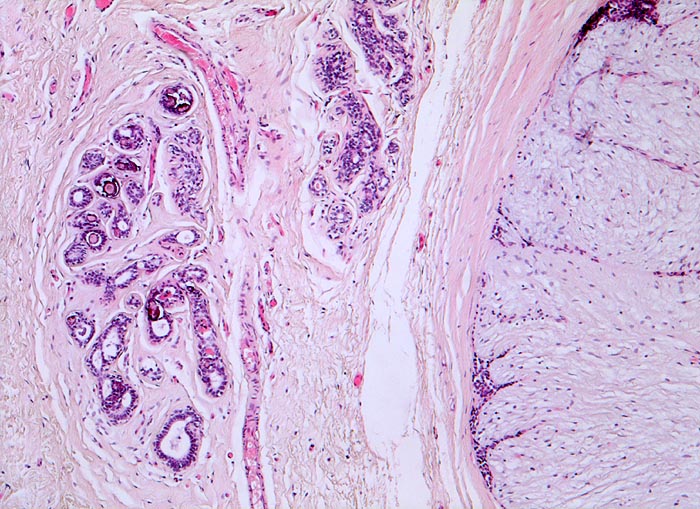

Fibroadenom der Mamma. Mikroverkalkungen.

Rechts im Bild das scharf begrenzte Fibroadenom bestehend aus reichlich zellarmem Stroma und komprimierten von Epithel ausgekleideten Gängen. Links davon leicht fibrosierte Drüsenläppchen, welche intraazinäre Mikroverkalkungen enthalten.

Scharf begrenzter frei beweglicher 3cm grosser derber Knoten im oberen äusseren Quadranten.

Mikroverkalkungen können auch in nicht neoplastischem Mammaparenchym auftreten, sind also nicht zwingend mit einem in situ Karzinom oder einem invasiven Karzinom assoziiert.